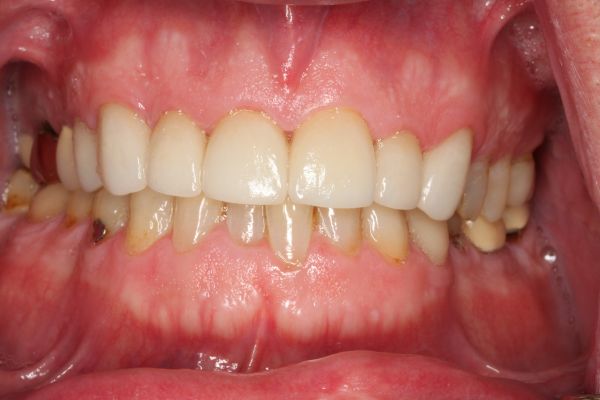

It’s never too late to restore and rejuvenate your smiles. After years of hiding her smile, this patient decided she had enough. With new upper and lower dental crowns and veneers on her front teeth, now she has the confidence to flash her pearly whites.

Crowns on upper front teeth 6-11 and lower front teeth 22-27 Crowns on the molars and bicuspids on the upper right and lower right. 3/4/5/28/29/30.

Crowns on lower front teeth 22-27.